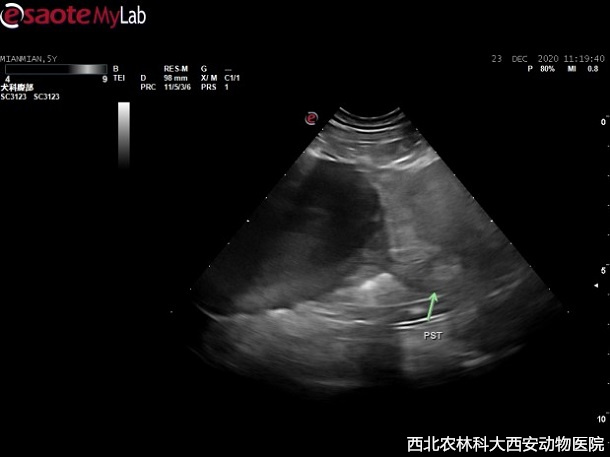

治療:經(jīng)與主人溝通,決定剖腹探查,分離粘連摘取占位,進(jìn)一步診斷并實施去勢術(shù)。術(shù)前對患犬的身體狀況進(jìn)行分級,ASA I級,給予麻前用藥,丙泊酚誘導(dǎo),吸入麻醉維持,實施剖腹探查占位摘除術(shù),術(shù)中抽放囊性結(jié)構(gòu),抽出液體為血水,經(jīng)查此占位與膀胱、前列腺和背側(cè)腹膜、腸系膜等均發(fā)生粘連,但無明顯組織來源見(圖2)。將摘除占位切開并放除內(nèi)部液體后,可見網(wǎng)狀結(jié)構(gòu)見(圖3)。手術(shù)期間至術(shù)后使用抗生素。占位送檢病理待查。

圖二 | 圖三 |